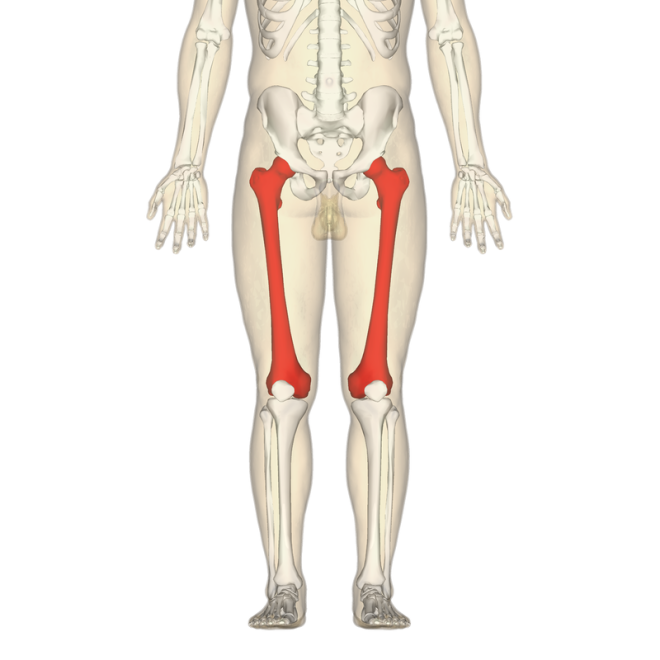

3. В свою очередь, самая длинная кость — бедренная. Она составляет около 27% от общего роста человека. Кроме того, бедренная кость считается одной из самых прочных (наряду с большеберцовой).